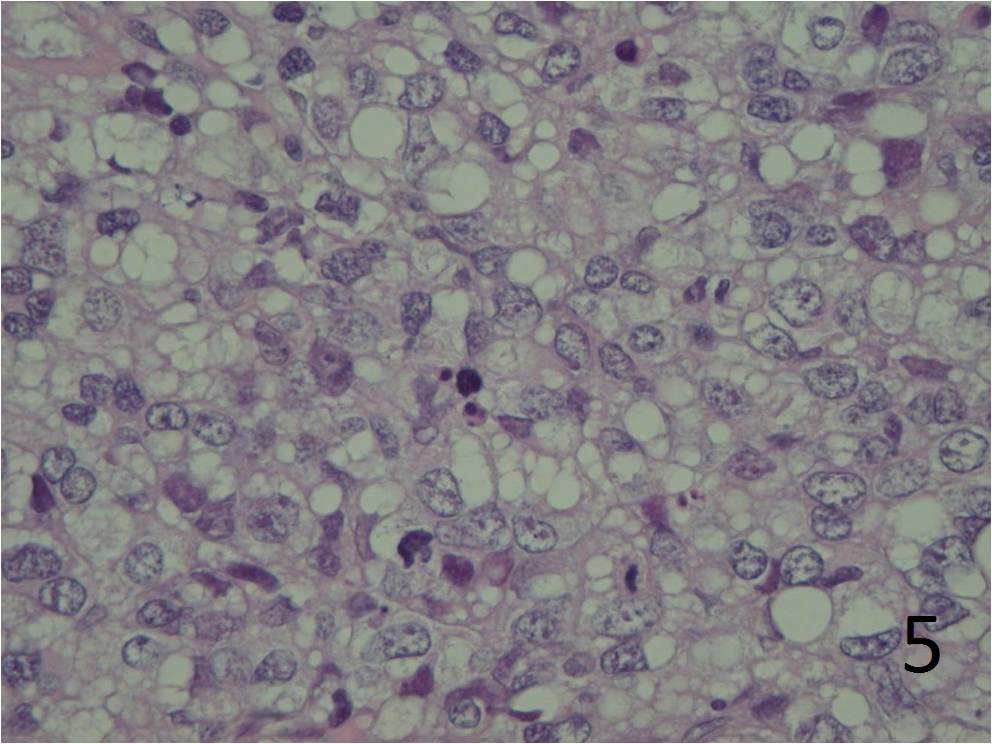

Moderately to markedly pleomorphic (Fig. 4 and 5)

Fig. 4 Microscopic: Intermediate and high (Fig. 5) power magnification show prominent pleomorphism, and many lipid vacuoles; cells are large and multinucleated. The lipoblasts are pleomorphic.